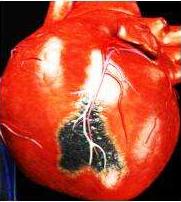

冠心病是指供应心脏本身的冠状动脉血管发生动脉粥样硬化病变而引起血管腔狭窄或阻塞,造成心肌缺血、缺氧、坏死而导致的一类心脏病,常常简称为"冠心病"。

当出现胸痛、胸闷症状,同时合并有高血压,高血脂,等心血管危险因素时,那么就需要高度考虑冠心病。冠心病的检查分为两大类,一类是无创检查,心电图,心脏超声,动态心电图,血糖,血脂等检查,通过这些检查,结合患者的症状,由心血管内科的专科医生进行评估可以初步进行冠心病诊断。另一种就是冠状动脉造影,目前是诊断冠心病的金标准,通过桡动脉或股动脉将一根微导管送至心脏冠状动脉进行造影,明确冠状动脉有无狭窄或堵塞,如果造影明确冠状动脉堵塞,我们可以同时进行冠状动脉支架植入术。所以针对那种症状特别典型的患者,我们推荐冠状动脉造影检查,因为冠状动脉造影既是一个检查,同时如果冠状动脉病变严重又可以进行下一步针对性治疗。

冠状动脉造影

冠状动脉造影血管图形